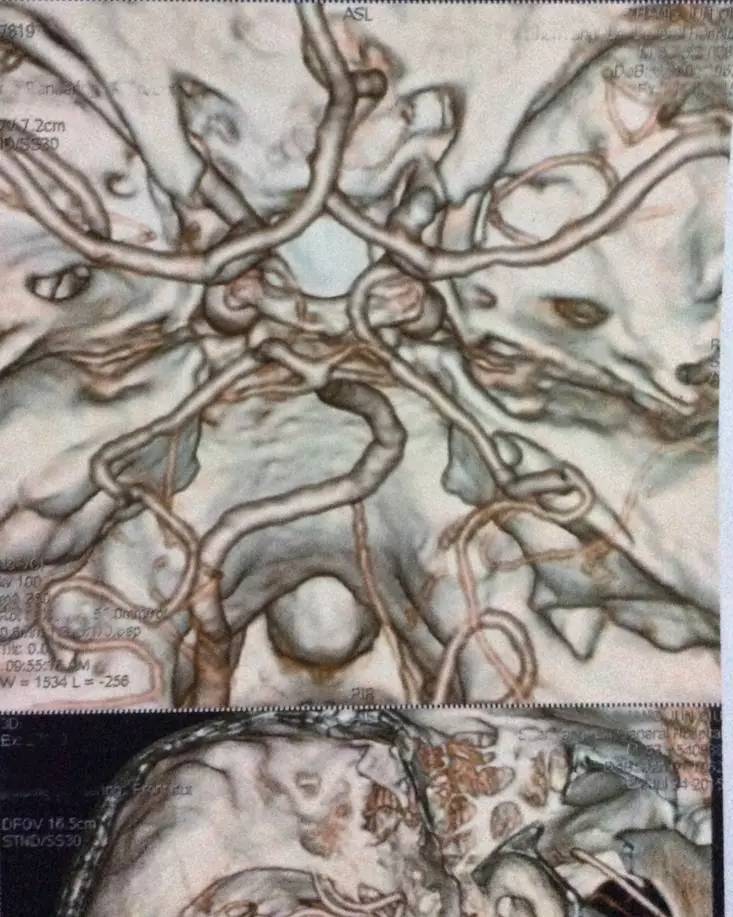

右侧椎动脉颅内段局限性显示纤细,余脑血管未见明显异常。

右颈内动脉近段混合斑块形成,管腔狭窄约20%;右椎动脉起始处非钙化斑块形成,管腔狭窄约40-50%,余颈部血管未见明显异常。

右侧椎动脉起始部存在中重度狭窄,但是需要血管造影检查更准确的判断其狭窄程度是否达到了重度。虽说左侧为优势椎,但是右椎有个优势的小脑后下动脉,因此提高了支架干预的倾向!此处支架的手术难度和风险不大,主要是术后一年内的支架再狭窄率较高(可高至20%左右)的问题需要特别强调。